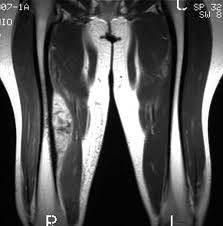

Entre los médicos generales australianos conocidos por solicitar con frecuencia imágenes de diagnóstico musculoesquelético, una auditoría individualizada y una intervención de retroalimentación, en comparación con ninguna intervención, disminuyó significativamente la tasa de pruebas de imágenes musculoesqueléticas dirigidas ordenadas durante 12 meses. JAMA, septiembre de 2022